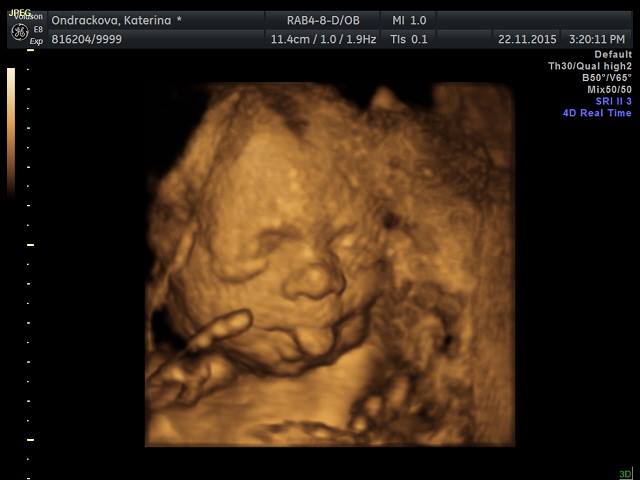

Ja byla na 3D vcera a supr :-) Mame video a 18 fotek. Ze zacatku to vypadalo tragicky, mimi oblicejem zaboreny v placente ale pak ho sestricka nasla z jinyho uhlu. Platila sem neco kolem 1300. Ted je nejlepsi doba na to jit kvuli velikosti mimi a mnozstvi plodovky. Tak sup holky ;-)

Ted su konecne na pc, tak prikladam vcerejsi ulovky

Jeeee, Kačenko, tak to nema chybu, ten jazyk je super :-D moc pekne vam to vyšlo. Mimiško je krasny. Až mě to 3D trochu mrzi ze nejdeme. Ja se zrovna chystam na tu cukrovku.

Gaga-Kacenka: Jůůů, krááásný, ten jazyk to se fakt povedlo ;)))!!! Tak už se taky moc těším, snad bude malá spolupracovat a nebude se schovávat ;).

.Kacko.. tak to fakt nema chybu ten jazyk :) hezke... a prvni fotka roztomila..